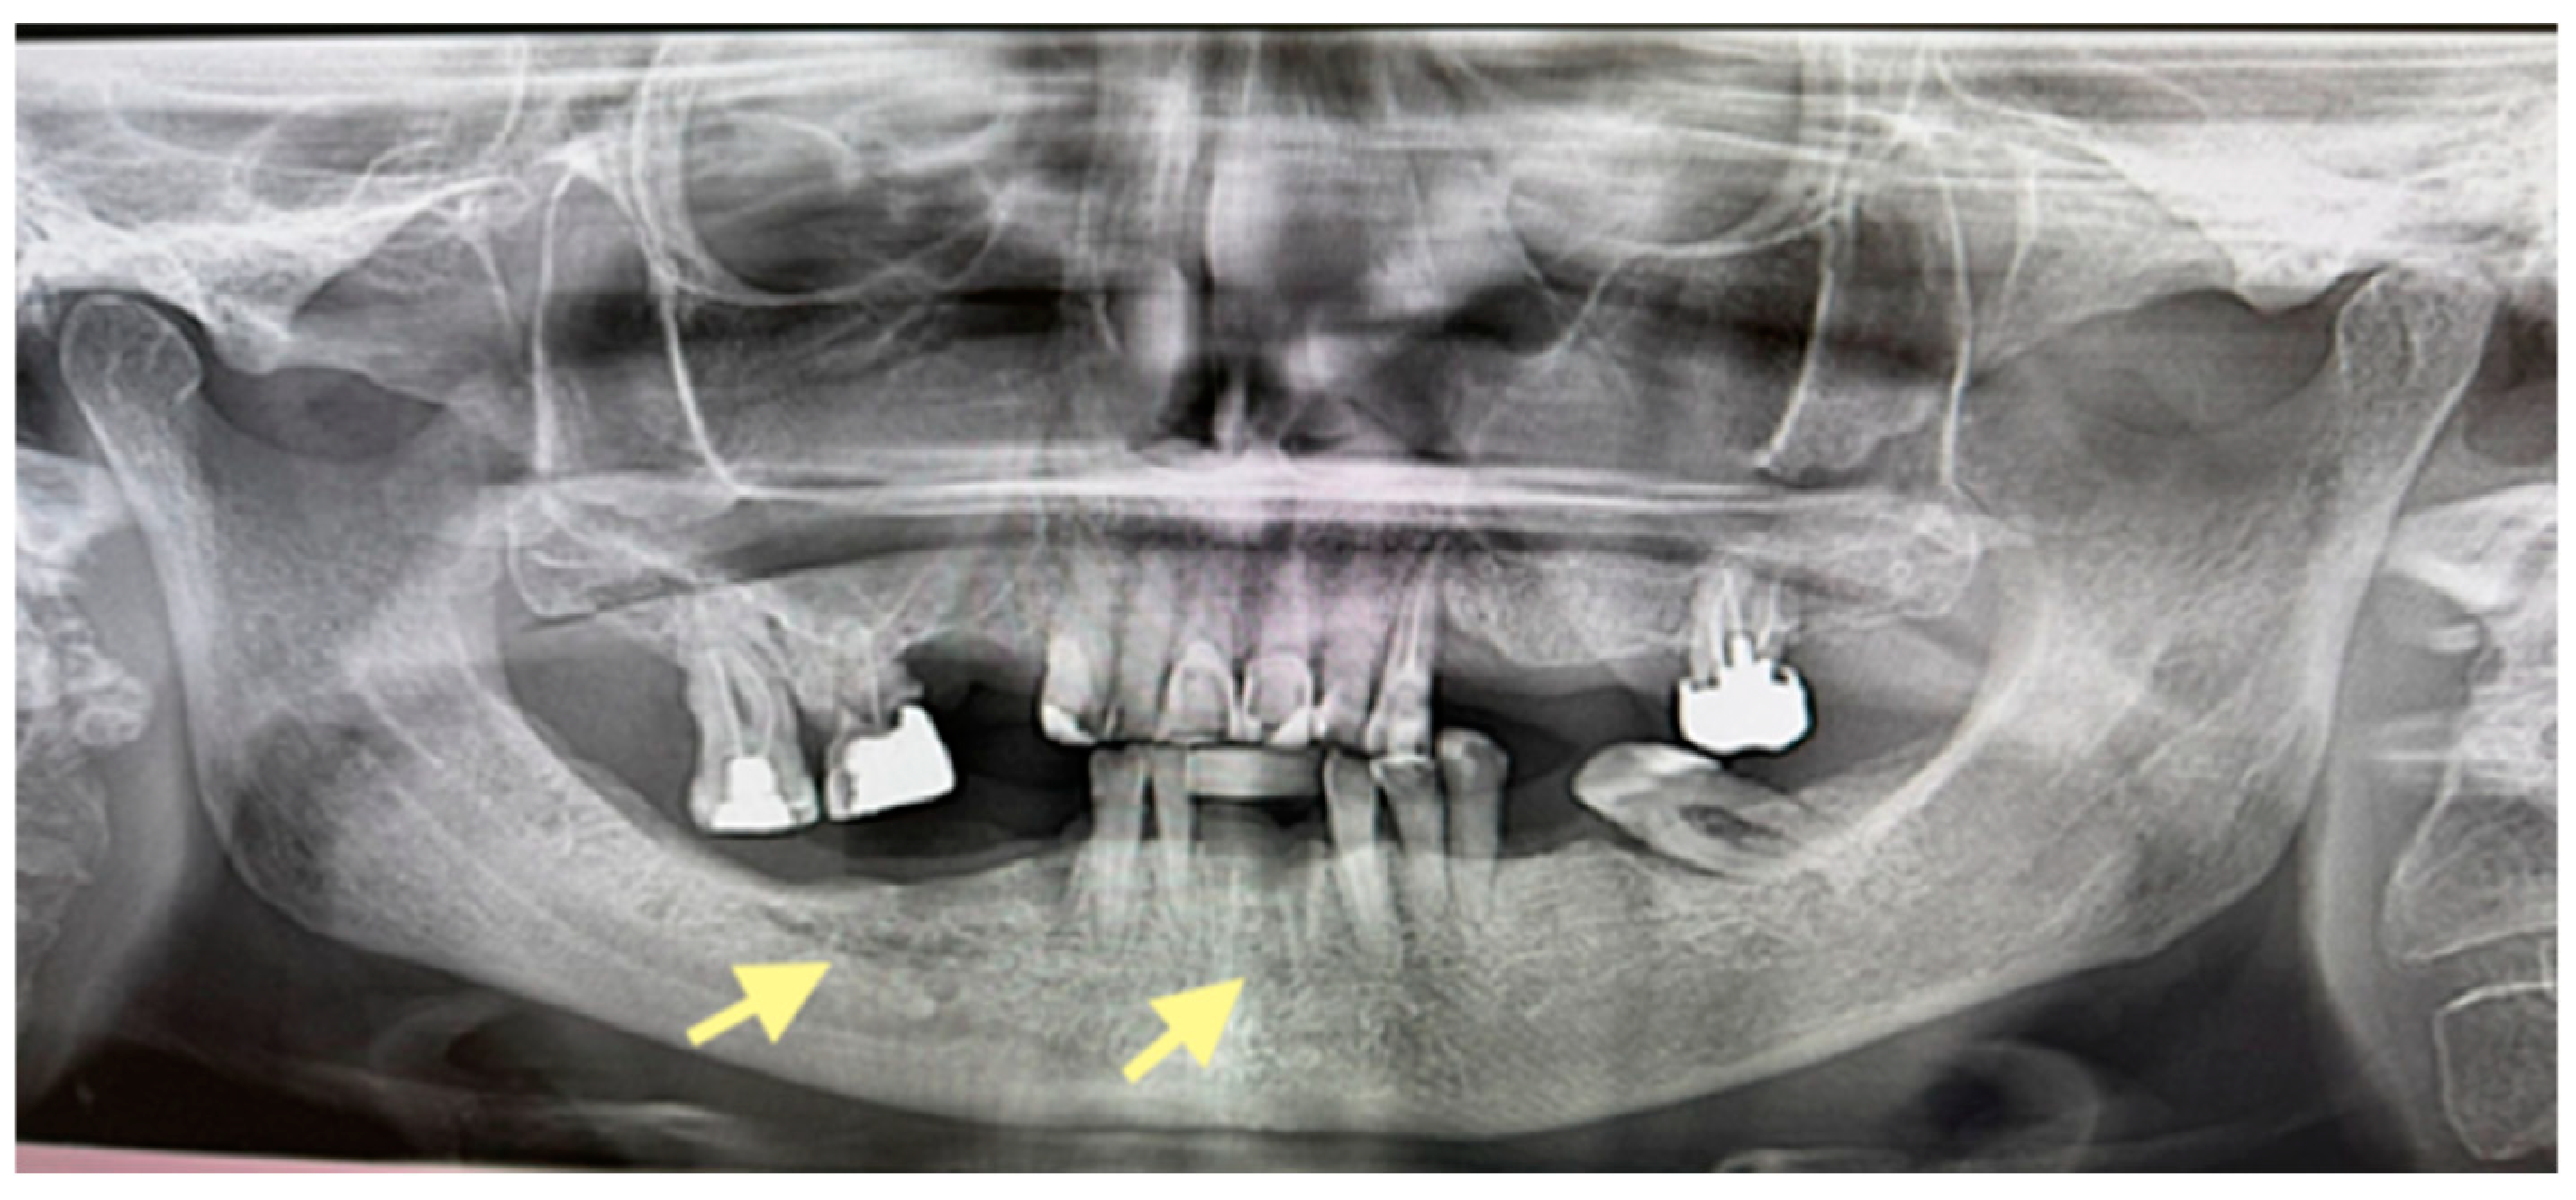

The third patient was a 75-year-old female with osteonecrosis of the mandible and maxilla in the fourth and in the second quadrant (see Figure 7, Figure 8 and Figure 9). The patient had third-stage jaw osteonecrosis. In 2023, the patient was diagnosed with osteonecrosis of the upper and lower jaw caused by antiresorptive therapy (until August 2021, the patient regularly used Zolendronic acid; then, this drug was replaced by the RANKL inhibitor Denosumab). The treatment was periodically complicated by submandibular and submental abscesses. In addition, due to the progression of the underlying disease, constant courses in chemotherapy were administered. The patient underwent three operations, which included sequestrectomy of the jaw with simultaneous use of A-PRF, antrotomy with revision of the maxillary sinus, closure of the oroantral communication, and opening and revision of abscesses of the soft tissues (see Figure 10 and Figure 11)

CT of the head and facial bones (16 December 2024).